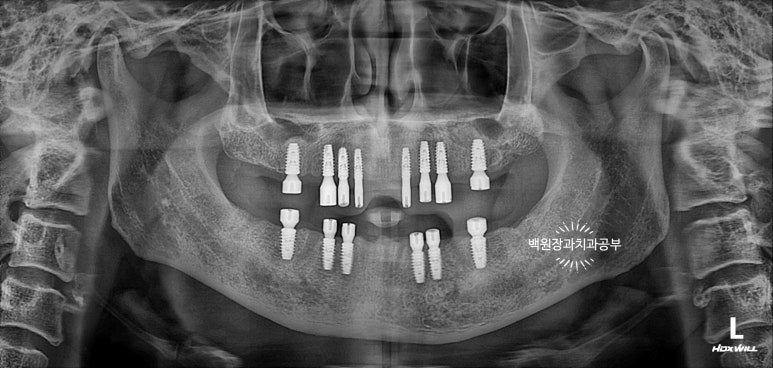

초진 치과 파노라마 사진

저희 환자분께서 처음 내원하셨을 당시 치과 파노라마 사진입니다.

성인의 치아 개수가 총 몇개인지 아시나요? 위턱 14개 아래턱 14개 총 28개입니다.

방문하셨을 당시 위턱은 전체 치아가 발치된 상태였고, 아래턱은 총 6개의 치아만 남아있었습니다.

남아있는 치아들도 치아의 옆면 (=인접면)에 충치가 있는 것으로 보아, 이를 뽑기 전에도 다수의 충치가 있으셨겠구나.. 라는 것을 짐작할 수 있었어요.